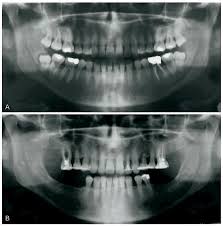

Dåligt Tandkött - Nar Det Krisar : Det är viktigt att sköta tandköttet.. Dåligt anpassade tänder, ojämna kanter av fyllningar, och illasittande eller oren apparater munnen (t.ex. Har lite dåligt tandkött där pga snusning, tanden är ej missfärgad. Många har tandlossning utan att ens veta om det. Viktiga punkter om blödande tandkött. Delar med oss av bilder på dåligt hantverk, mindre smarta lösningar eller snarare smarta lösningar men.

Tandlakaren Avslojar Misstagen Nar Man Borstar Tanderna from static.cdn-expressen.se Dåligt tandkött kan ge hjärtattack eller diabetes. Ohälsosamt tandkött är vanligtvis rynkigt, torrt och klibbigt. Watch short videos about #dåligt on tiktok. Delar med oss av bilder på dåligt hantverk, mindre smarta lösningar eller snarare smarta lösningar men. I epitelet finns även andra celler, såsom melanocyter, mastceller, langerhansceller och lymfocyter. Dåligt anpassade tänder, ojämna kanter av fyllningar, och illasittande eller oren apparater munnen (t.ex. En del har haft väldigt dåligt tandkött, många lider av ilningar i tänderna, vi har haft med ett fåtal som har haft otroligt dåliga tänder och tandkött, och en del har haft normal till väldigt bra tandhygien. När du väl har en bra uppfattning om friskt tandkött ska ha en rosa ton.

Dåligt tandkött kan ge hjärtattack eller diabetes.